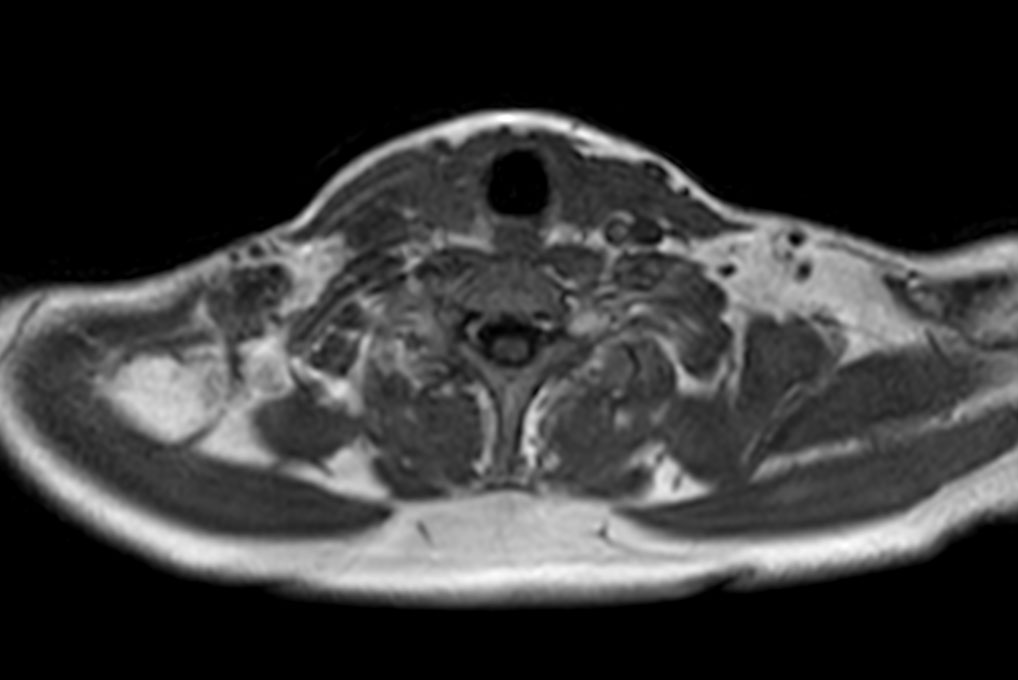

Axial T2w mDIXON XD TSE (In Phase)